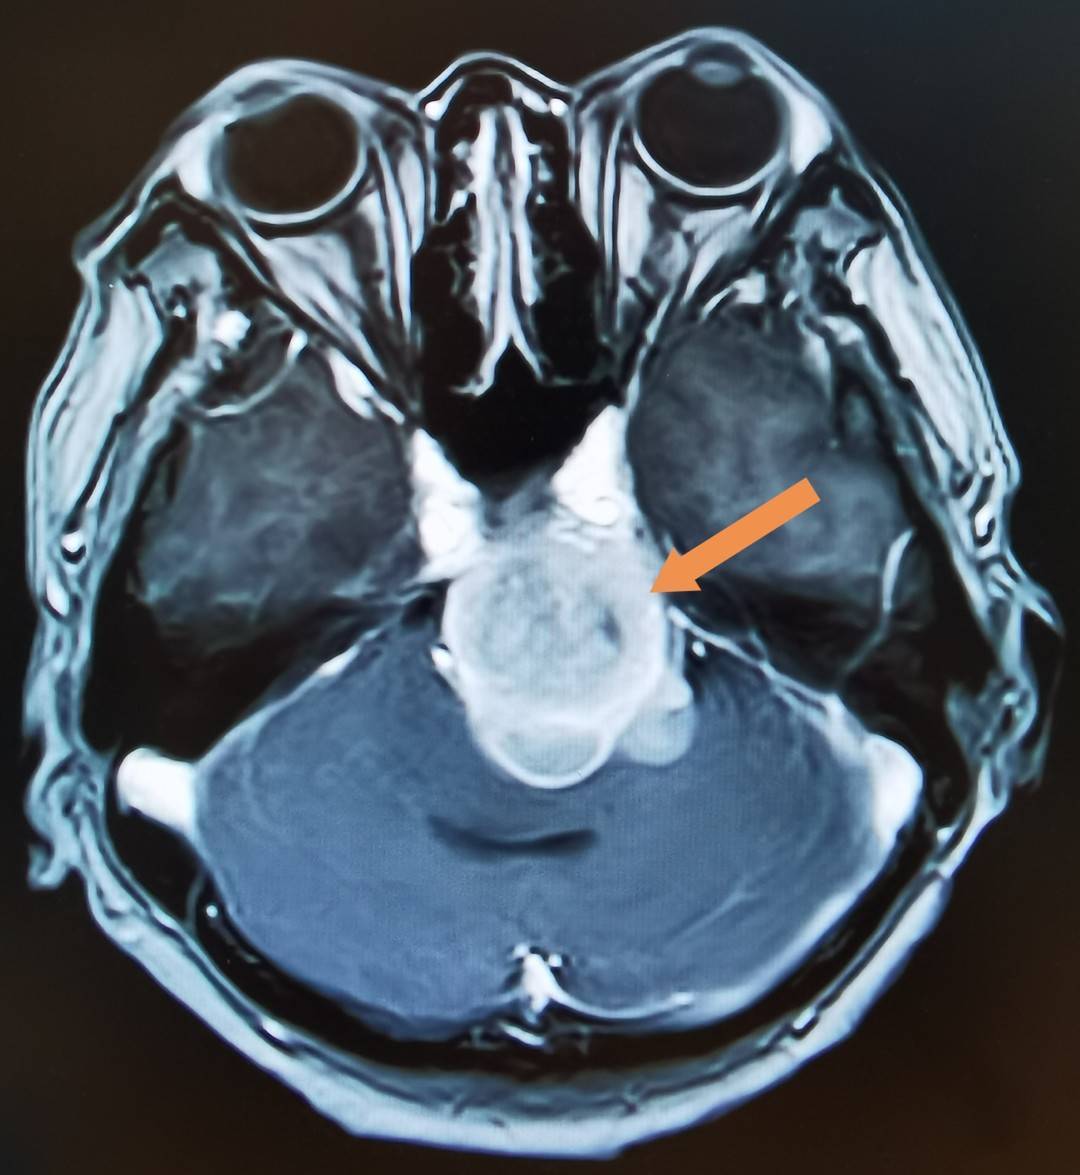

岩斜区脑膜瘤 - 好大夫在线

图片尺寸3456x4608